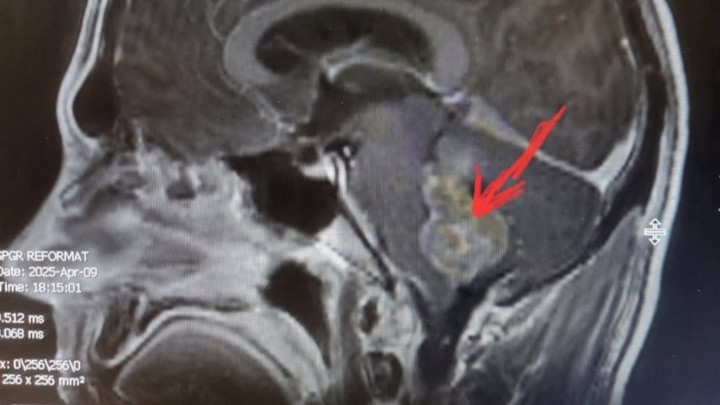

I’m reaching out to ask for help for my brother, Stepan, who recently underwent emergency brainstem surgery. While we are incredibly grateful that the surgery was successful, his journey to recovery is going to be long, challenging, and filled with uncertainty.